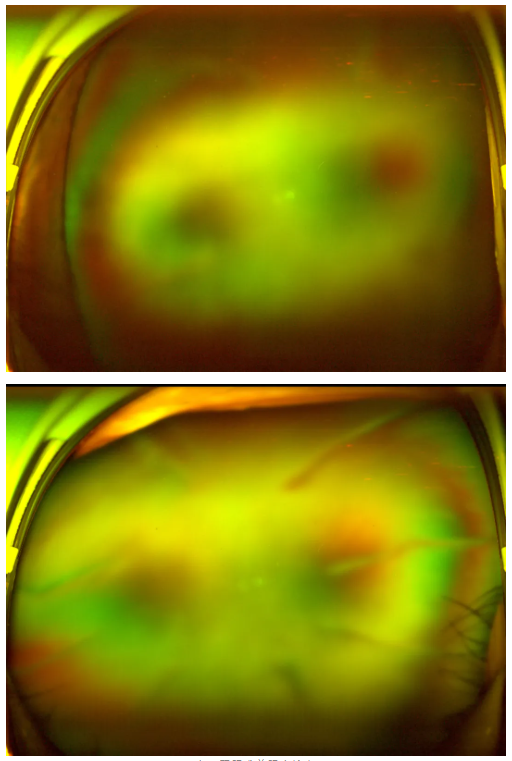

老王雙眼術(shù)前眼底檢查

“別灰心,好好配合治療,你還是有很大機(jī)會(huì)能恢復(fù)部分視力的。”王曉波主任的話像一顆定心丸,讓老王懸著的心得以放松。在醫(yī)生的指導(dǎo)下,老王先積極穩(wěn)定血糖,為后續(xù)治療打下堅(jiān)實(shí)基礎(chǔ),隨后多次轉(zhuǎn)機(jī)重返廈門眼科中心辦理入院,準(zhǔn)備接受針對(duì)性治療。

王曉波主任告知老王:術(shù)后復(fù)查眼底顯示,其糖尿病視網(wǎng)膜病變并不嚴(yán)重,因此視力得以得到明顯改善與提升。當(dāng)初堅(jiān)持治療、不輕言放棄,是非常正確的選擇!

糖尿病視網(wǎng)膜病變